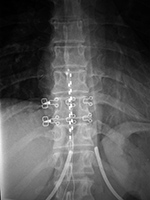

| Lumbar spine pedicle plates and screws and Brantigan disk cage (arrow) |

Brantigan disk cage |

| Note the associated solid posterolateral bony fusion masses |